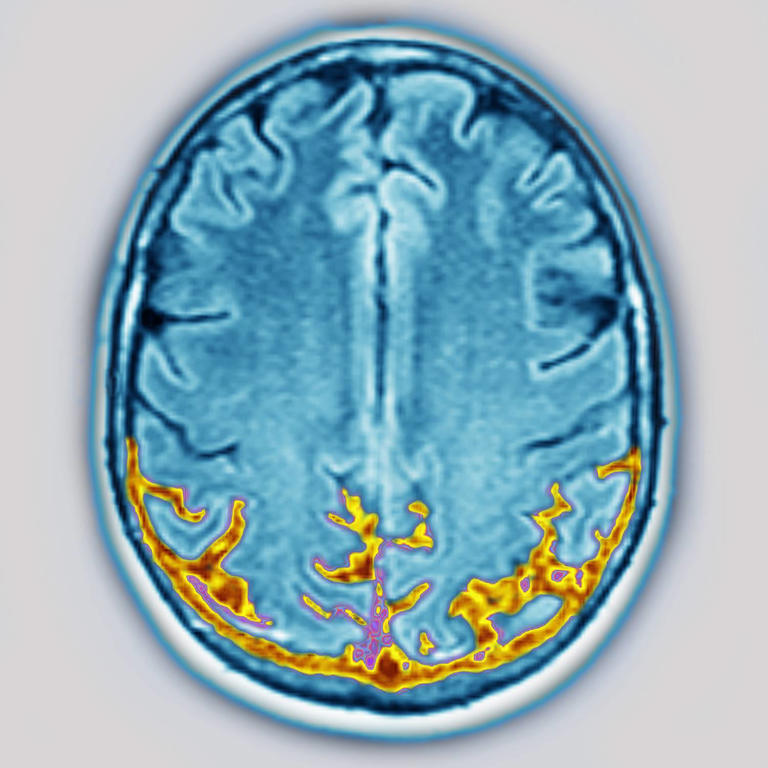

Felnőtteknél az apraxia leggyakoribb kiváltó oka valamilyen agyi sérülés vagy betegség: stroke, fejsérülés, agydaganat, illetve neurodegeneratív kórképek – például demencia. Egyes esetekben epilepszia vagy agyi fertőzések is állhatnak a háttérben. Olykor azonban nem sikerül pontosan meghatározni a kiváltó tényezőt.

Az apraxia jelenlétét neurológus állapítja meg. A vizsgálat során különféle, hétköznapi cselekvéseket kér a betegtől: például zárjon be egy ajtót kulccsal, fújjon levegőt, vagy használjon képzeletbeli eszközöket. A feladatok célja az, hogy feltérképezzék, a beteg képes-e értelmezni és kivitelezni az instrukciókat. A diagnózis megerősítésére gyakran képalkotó vizsgálatokra –például CT-re vagy MRI-re – is sor kerül, különösen akkor, ha agysérülés gyanúja merül fel. Amennyiben a beszéd is érintett, logopédus vizsgálata is szükséges lehet.